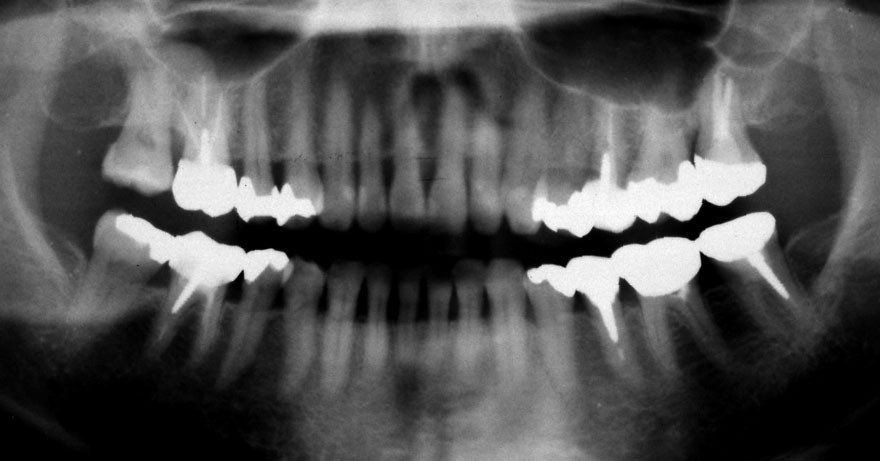

開始年齢 30代

初診時 30歳 女性 平均歯槽骨喪失量:1.46mm

22年後 52歳

平均歯槽骨喪失量:1.55mm

22年間喪失量:-0.09mm

年間喪失速度:-0.004mm

(ケア頻度:1.76ヵ月ごと)